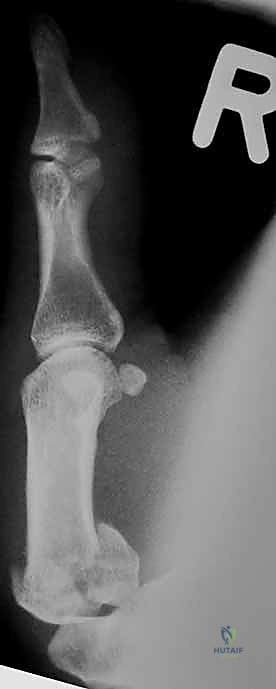

هو أشهر أنواع كسور قاعدة الإبهام وأكثرها تعقيداً. وهو كسر داخل المفصل يتميز بوجود خط كسر مائل يفصل شظية صغيرة من الجانب الراحي الزندي (Volar-Ulnar) لقاعدة المشط الأول.

* الديناميكا المرضية: المشكلة الكبرى في كسر بينيت هي "القوى العضلية المعاكسة". بينما تظل الشظية الصغيرة ثابتة في مكانها بفضل رباط المنقار القوي، تقوم عضلة "مبعدة الإبهام الطويلة" (Abductor Pollicis Longus - APL) بسحب الجزء الأكبر المتبقي من عظم المشط إلى الأعلى والخلف، مما يؤدي إلى خلع جزئي (Subluxation) للمفصل.

* هذا الكسر غير مستقر بطبيعته ويحتاج دائماً إلى تدخل لتثبيته.